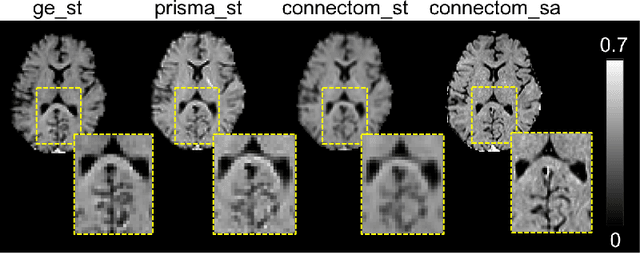

Abstract:Prior work on the Image Quality Transfer on Diffusion MRI (dMRI) has shown significant improvement over traditional interpolation methods. However, the difficulty in obtaining ultra-high resolution Diffusion MRI scans poses a problem in training neural networks to obtain high-resolution dMRI scans. Here we hypothesise that the inclusion of structural MRI images, which can be acquired at much higher resolutions, can be used as a guide to obtaining a more accurate high-resolution dMRI output. To test our hypothesis, we have constructed a novel framework that incorporates structural MRI scans together with dMRI to obtain high-resolution dMRI scans. We set up tests which evaluate the validity of our claim through various configurations and compare the performance of our approach against a unimodal approach. Our results show that the inclusion of structural MRI scans do lead to an improvement in high-resolution image prediction when T1w data is incorporated into the model input.